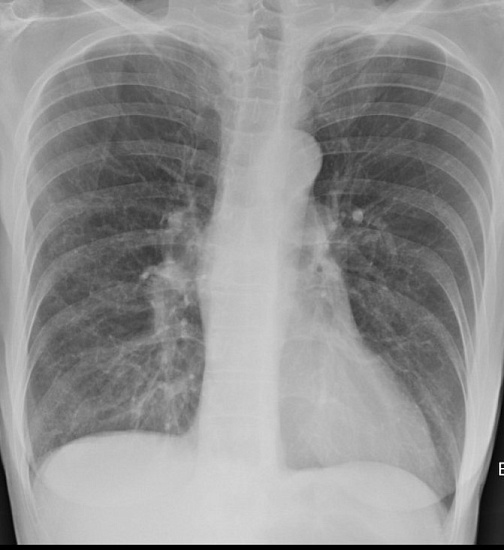

1. Рентгенография органов грудной клетки в 2-х проекциях - скрининговое исследование органов грудной клетки, выполняемое в двух проекциях.

2. Рентгенография легких в прямой проекции – скрининговое исследование органов грудной клетки, выполняемое в двух проекциях.